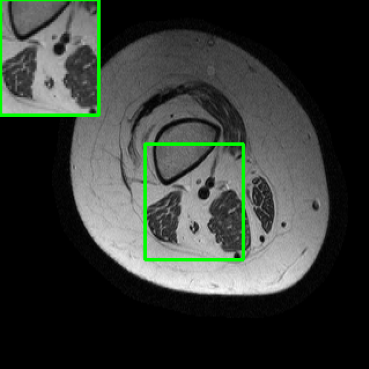

Performance in the Presence of Planted Features: To assess the capability of LONDN-MRI for accurately reproducing image attributes not found in the training set (a common scenario when detecting pathologies, etc.), we embedded artificial features into a knee image from the fastMRI dataset, drawing inspiration from recent work [44]. We performed 4x undersampling in k-space and reconstructed with the MoDL network (with UNet denoiser) that was trained using 3000 images. In Fig. 15, we observe that LONDN-MRI produces sharper reconstruction of image features and better PSNR compared to the globally trained network. The details or edges of the planted features are better preserved in LONDN-MRI. Moreover, LONDN-MRI provides similar image quality with and without the planted features (Fig. 5), whereas, the globally trained network degrades significantly. This indicates the relatively improved stability and generalizability of the proposed method.

| Ground Truth | LORAKI | Global | LONDN-MRI | LONDN-MRI | Oracle |

| (1 iteration) | (2 iterations) | ||||

![]() |

| PSNR = dB | PSNR = 31.45 dB | PSNR = 32.15 dB | PSNR = 32.72 dB | PSNR = 33.15 dB | PSNR = 33.22 dB |